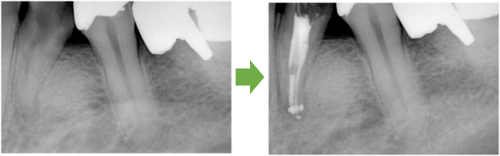

抜髄 左の前歯 川口の歯科 歯医者 さかえ歯科クリニック

2014年12月16日

川口の歯科 歯医者 さかえ歯科クリニック